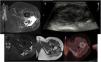

Case 3A 46-year-old male involved in a traffic accident ten years previously who had subsequently developed a tumour on the affected leg that had resolved spontaneously.

The patient was referred from another centre for suspicion of liposarcoma, and reported pain and a tumour in the same region as the accident, both of which had begun one year previously.

An ultrasound (Fig. 3A) and MRI (Fig. 3B) were performed, revealing an extensive lesion in the subcutaneous cellular tissue of the lateral aspect of the pelvis and root of the right thigh. The lesion was polylobulated and surrounded by a markedly hypointense thick capsule on all sequences. The content was highly heterogeneous, with a markedly hyperintense component on T1-weighted sequences.

A) Ultrasound and B) MRI: lesion in the subcutaneous cellular tissue of the lateral aspect of the pelvis and root of the right thigh, polylobulated, surrounded by a markedly hypointense thick capsule (→) on all sequences. The content is highly heterogeneous, with a hyperintense component (*) on the T1-weighted sequences. C) After intravenous contrast administration, central filiform enhancement is seen (→), with no peripheral or nodular enhancement.

After administration of paramagnetic contrast (Fig. 3C), central filiform enhancement was observed with no peripheral or nodular enhancement.

A complete surgical excision was carried out which confirmed the CEH diagnosis histologically and resulted in a favourable evolution.